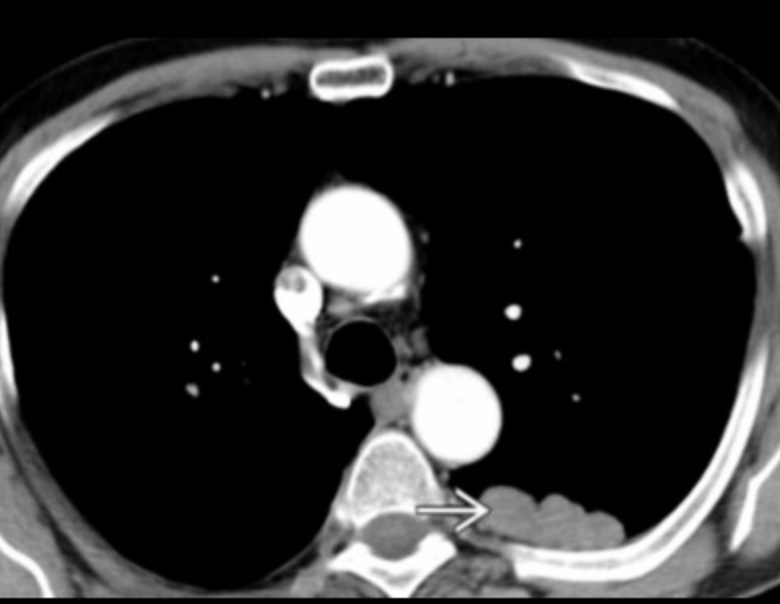

Thoracic splenosis

• Auto-transplantation of spleen after a trauma to the pleural surface

• Looks like lobulated left sided pleural based mass